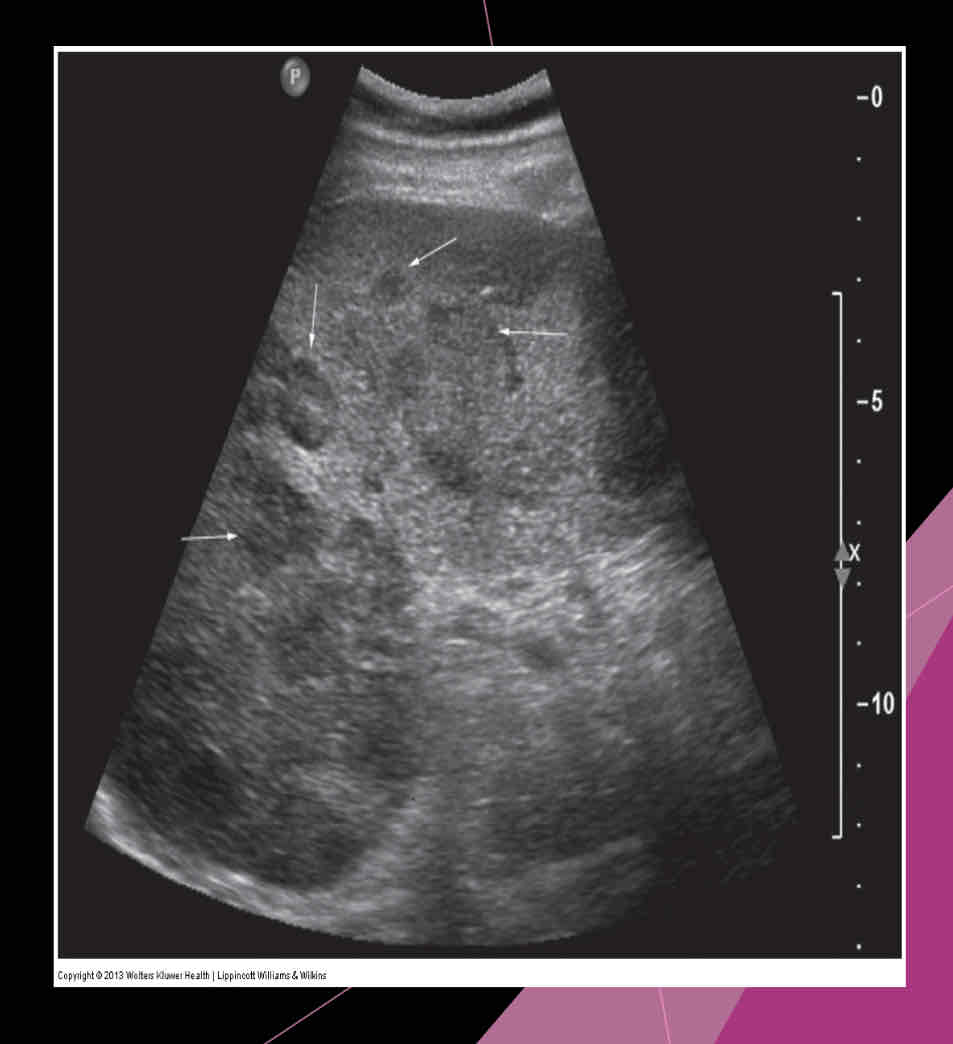

What is the measurement for enlarged spleen (splenomegaly)?

>13cm in length

What is the most common splenic abnormality observed sonographically?

enlargement (splenomegaly)

What is the most common cause of splenomegaly?

Portal hypertension due to cirrhosis is most common cause in adults

With splenomegaly: when enlarges, it extends

anteriorly, medially and inferiorly

What are the four sonographic patterns of lymphoma in the spleen?

•Diffuse, marked splenomegaly, patchy inhomogeneity

•Multiple small hypoechoic lesions

•Multiple large lesions

•Bulky solid mass lesions